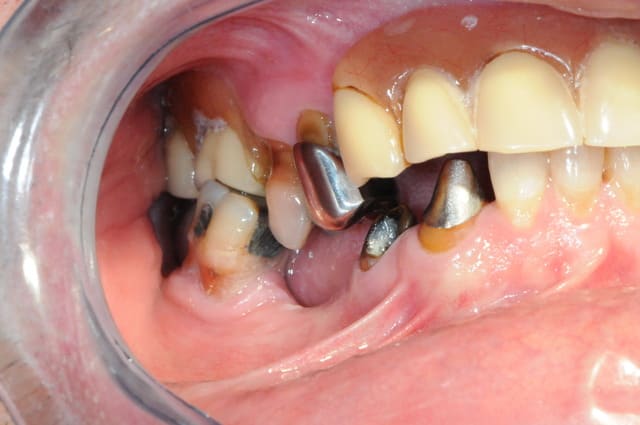

bien sure il faut tout revoir, l'occlusion, la DV, la courbe occlusale, la ligne du sourire...

extraction: 14-15-23-44 et 36 (ou amputation, mais à quoi bon ?)

reprendre la courbe occlusal avec des céram sur 43-46-33-34

bridge sur implant sur 44 -46 et 35-36 (ou 35-37?)